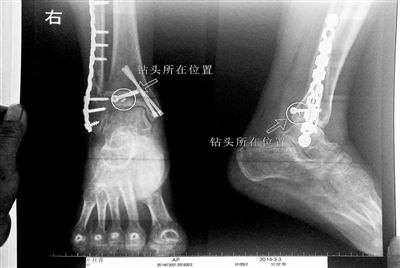

胡女士的腿部X光圖

看著X光片中自己腿內(nèi)的異物,胡女士就感到莫名的擔(dān)憂。胡女士于2013年3月在北京市豐臺(tái)區(qū)右安門醫(yī)院進(jìn)行了一次骨折手術(shù),術(shù)后醫(yī)生才發(fā)現(xiàn)手術(shù)時(shí)用來(lái)打眼用的鉆頭不慎遺留在了胡女士的骨頭中,并且無(wú)法取出。

近日,在豐臺(tái)區(qū)右安門醫(yī)院,北京青年報(bào)記者見到了胡女士,她走起路來(lái)顯得一瘸一拐,腿腳并不利索。在她帶來(lái)的X光片上,可以清晰地看到,有一個(gè)異物存在于腿內(nèi)部。

“我當(dāng)時(shí)就嚇蒙了,怎么會(huì)有一個(gè)鉆頭在骨頭里?”胡女士余悸未消地說(shuō),第二天拍攝的X光片顯示,2厘米左右的鉆頭遺留在她右腳腳踝上部的骨頭內(nèi)。

胡女士說(shuō),當(dāng)時(shí)旁邊的醫(yī)生勸慰自己,稱鉆頭留在腿里并不會(huì)有什么問題。出院后,胡女士每個(gè)月都會(huì)來(lái)醫(yī)院做復(fù)查,拍X光片。她說(shuō),每次都能夠清晰地看見自己骨頭里的那個(gè)明晃晃的“小東西”。

“按照照片里的位置,相對(duì)來(lái)說(shuō)是沒有害的?!必S臺(tái)區(qū)右安門醫(yī)院醫(yī)務(wù)科徐主任告訴胡女士,任何事情都無(wú)法做出絕對(duì)的判斷,但是從目前情況而言,鉆頭對(duì)于腿部沒有更多的危害。她介紹說(shuō),臨床上遇到過(guò)很多這種情況,諸如鋼板釘子,有時(shí)候釘子滑扣,無(wú)法取下,也只能存在體內(nèi),但是這些都是個(gè)別情況。

“留在她腿里的鉆頭確實(shí)無(wú)法取出?!毙熘魅谓忉屨f(shuō),按常理說(shuō),鉆頭不應(yīng)該斷在里面,但現(xiàn)在事情確實(shí)發(fā)生了。鉆頭沒有折在關(guān)節(jié),而是在跖骨內(nèi),跖骨主要起支撐作用,不像關(guān)節(jié)那樣起活動(dòng)作用,而且這個(gè)部位比較質(zhì)密,并非像肌肉要經(jīng)常活動(dòng)受到擠壓。